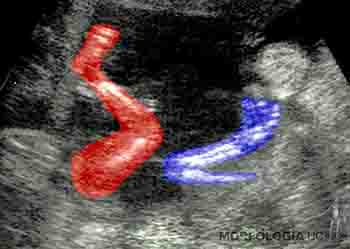

En el quinto mes, los miembros inferiores crecen y adquieren una proporción más armónica. A esta edad la madre percibe los movimientos fetales y es posible auscultar los latidos fetales. La piel está cubierta por una secreción grasosa llamada unto sebáceo o vérnix caseosa. Esta capa grasosa evita la maceración de la piel del feto que flota en el líquido amniótico. En este período se canalizan los canales anal y vaginal, y comienza la migración del testículo. Ecográficamente ya son visibles los riñones y la vejiga urinaria (Figuras 2-21a y b).

Figura 2-21a

Figura 2-21b